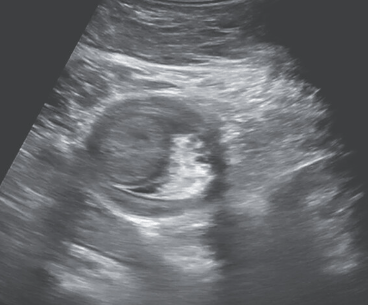

Image from NEJM: Colocolonic Intussusception

“Colonic intussusception is a rare cause of intestinal obstruction in children, and most cases are ileocolic rather than colocolonic. A pathologic lead point, typically a juvenile polyp, is present in the majority of cases.” In this case, panel D shows a 2.5 cm pedunculated polyp which was thought to be the lead point.